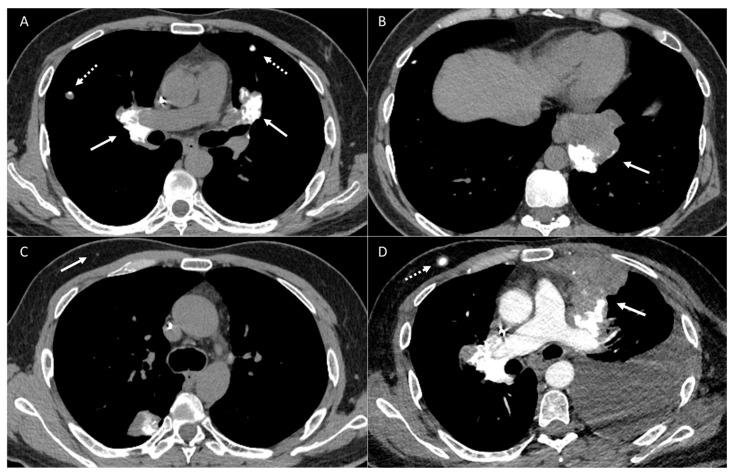

Osteosarcoma, a primary bone malignancy in children and adolescents, frequently metastasizes to the lungs, contributing significantly to morbidity and mortality. At diagnosis, 15-20% of patients present with detectable lung metastases. Chest computed tomography (CT) is vital for the early detection and monitoring of these metastases. Lung involvement typically presents as multiple nodules of varying sizes and can include atypical features such as cavitation, cystic lesions, ground-glass halos, intravascular tumor thrombi, and endobronchial disease. Pleural metastasis often occurs alongside pulmonary disease, and complications like spontaneous pneumothorax may arise. Additional findings may include thoracic lymphadenopathy, cardiac tumor thrombus, and chest wall deposits. Familiarity with these imaging patterns is essential for radiologists to ensure timely diagnosis and effective management. This review highlights the critical role of chest CT in detecting and characterizing osteosarcoma metastasis.

骨肉瘤是儿童和青少年常见的原发性骨恶性肿瘤,常转移至肺部,对发病率和死亡率有显著影响。在诊断时,15%至20%的患者出现可检测到的肺转移。胸部计算机断层扫描(CT)对于这些转移灶的早期检测和监测至关重要。肺部受累通常表现为大小不一的多个结节,可包括一些非典型特征,如空洞形成、囊性病变、磨玻璃晕、血管内肿瘤血栓和支气管内病变。胸膜转移常与肺部疾病同时发生,可能出现自发性气胸等并发症。其他表现可能包括胸内淋巴结肿大、心脏肿瘤血栓和胸壁转移灶。放射科医生熟悉这些影像学表现对于确保及时诊断和有效治疗至关重要。本综述强调了胸部CT在检测和鉴别骨肉瘤转移方面的关键作用。